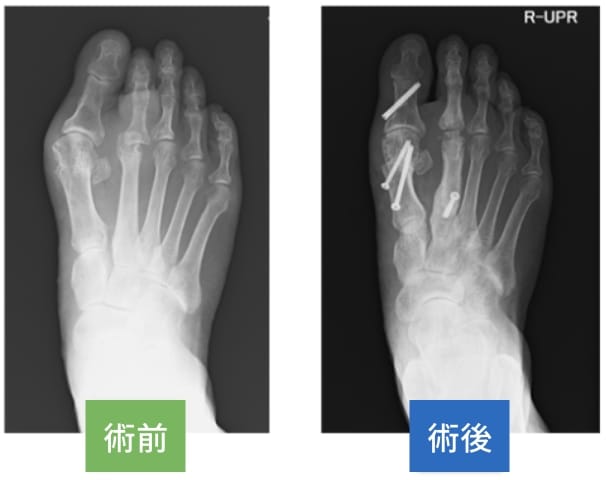

足の親指(母趾)が外側に曲がって痛みをきたす疾患です。親指(母趾)が2番目の指(趾)の下に潜り込むことで、2番目の指(趾)が変形して痛みがでたり、足の裏にタコ(胼胝)ができて痛みをだすことがあります。

装具や靴、運動療法などの保存的治療が基本ですが、これらで症状が軽減しない場合には骨を切って動かす手術を行います。病状により親指(母趾)以外の指(趾)も手術を行います。最近では経皮的に小さな傷で行っています。

矢印は経皮的手術の傷痕です。